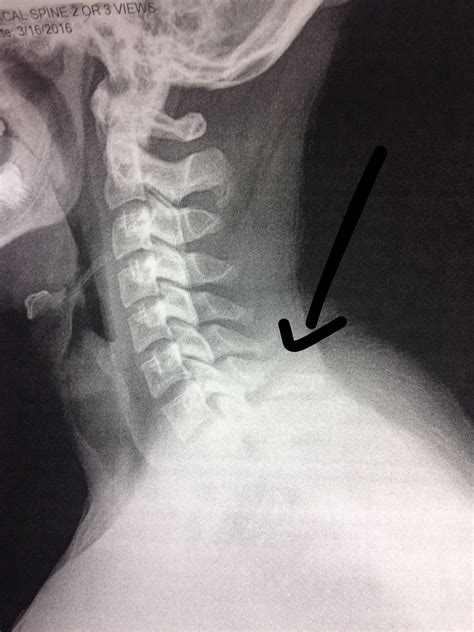

Understanding the intricacies of the human spine is crucial for anyone involved in healthcare, fitness, or anatomy. One of the key features of the spine is the spinous process, a bony projection that extends backward from each vertebra. In some cases, the spinous process is bifid, meaning it is split into two parts. This characteristic can have significant implications for diagnosis and treatment in various medical contexts.

The spinous process is a prominent feature of the vertebrae, serving as an attachment point for muscles and ligaments. It plays a crucial role in the stability and movement of the spine. The spinous process is typically a single, continuous structure, but in certain vertebrae, it can be bifid, meaning it is divided into two distinct parts.

When the spinous process is bifid, it means that the bony projection is split into two separate parts. This condition can occur in various vertebrae along the spine, but it is most commonly observed in the lower thoracic and lumbar regions. The bifid spinous process can be a normal anatomical variation or it can be associated with certain medical conditions.

Diagnosing a bifid spinous process typically involves a combination of physical examination and imaging studies. X-rays, CT scans, and MRI scans are commonly used to visualize the spine and identify any abnormalities. These imaging techniques can provide detailed images of the vertebrae, allowing healthcare providers to determine if the spinous process is bifid and to assess the extent of the condition.